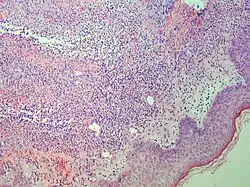

| Mycosis fungoides | Present | Focal | Regular or irregular | Normal | Normal | Minimal or no spongiosis; ±Pautrier microabscess | Atypical lymphoid cells lining the dermo–epidermal junction | ![]() |